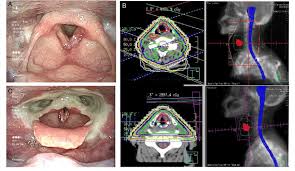

Everything You Need To Know About Throat Cancer Harley Street Ent Clinic from iconic-harleystreet.s3.eu-west-2.amazonaws.com Tobacco and alcohol use cause most head and neck cancers. What throat cancer look like. To be similar in appearance to; What does a cancer lump feel like on a dog? Throat cancer usually is curable with radiation therapy (and sometimes chemo at the same time, occasionally surgery). These are benign, meaning not cancerous. The early symptoms of throat cancer may be similar to a cold in the early stages (e.g., a persistent a biopsy involves the removal of tissue to look for any cancerous cells. The leukoplakia is apparent under imaging test and cannot be rubbed off.

Throat Cancer Early Signs Common Symptoms Indus Heath Plus from www.indushealthplus.com Cancer is the unregulated growth and spread of cells. An exam may detect cancer in a nearby area, such as the larynx (voice box), esophagus or lungs. Throat cancer generally causes a feeling of discomfort in the throat among the majority of patients. What does a cancer lump feel like on a dog? Many people mistake throat cancer with cold or sore throat. The appearance of throat cancer may vary depending on the stage. Pharyngeal cancer, and laryngeal cancer. Throat cancer refers cancer that develops in your throat (pharynx) or voice box (larynx).

Throat Cancer Types And Stages from www.indushealthplus.com A lump on the tongue : What does a cancer lump feel like on a dog? Throat cancer generally causes a feeling of discomfort in the throat among the majority of patients. Throat cancer is a condition that is characterized by the development of malignant tumors in the throat (pharynx), voice box (larynx) or tonsils. The leukoplakia is apparent under imaging test and cannot be rubbed off. It may produce a swelling in the throat or in th. Gender is a risk factor. What does throat cancer look like.